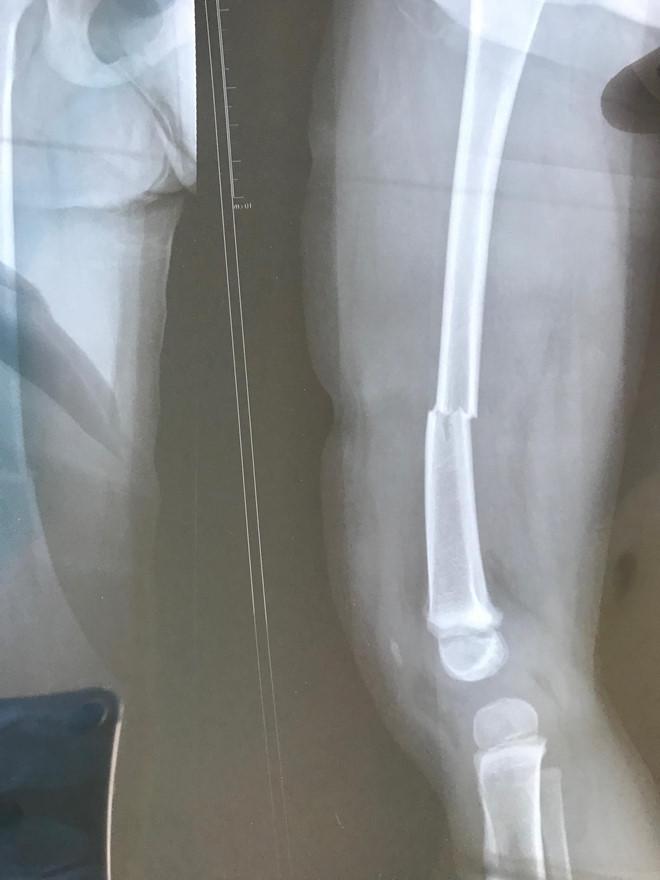

Ảnh chụp X-quang cháu bé gãy xương đùi bên trái. Ảnh: GĐCC.

Các bác sĩ cho biết M.A. bị gãy xương đùi bên trái do va đập mạnh, cần nẹp sơ cứu để phẫu thuật.